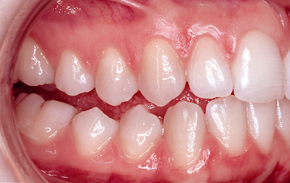

Zahnfehlstellung

Tiefbiss (tiefer Biss)

Die oberen Schneidezähne überlappen die unteren

Schneidezähne mehr als 3 mm und man sieht die unteren

Schneidezähne kaum noch [24].

Beim Tiefbiss überdecken die oberen Schneidezähne

die unteren Schneidezähne fast komplett.

Man sieht die unteren Schneidezähne kaum noch (Foto

von Praxis Dr. Kuster).